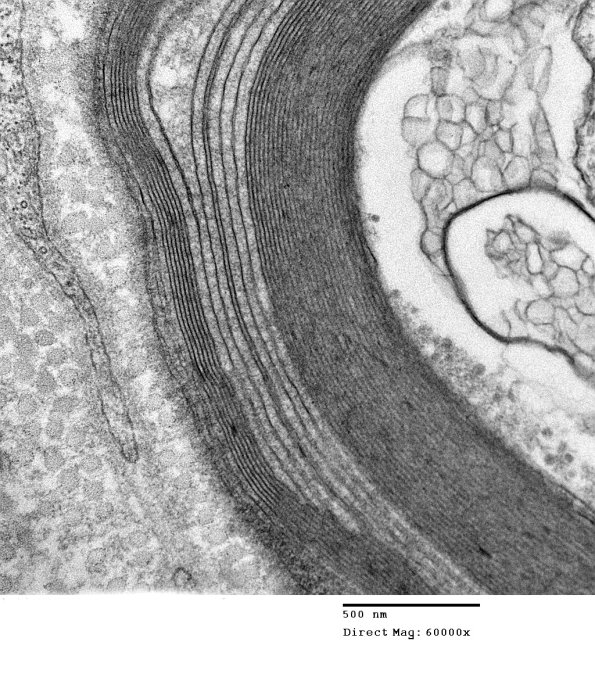

An example of wide-spaced myelin in which there is a varying degree of the involvement of the lamellae. In this case the low magnification image is subtle; although higher magnification reveals the WSM. (electron micrographs).